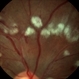

- A 73-year-old woman with macular pucker underwent a pars plana vitrectomy with membrane peeling. Additionally the patient suffers from diabetic retinopathy after being diagnosed with type 2 diabetes mellitus sixteen years ago. Prior to the procedure she was treated with a series of intravitreal Bevacizumab-injections due to diabetic macular edema. There was no history of a proliferative DRP. During the vitrectomy a branch of an obliterated NVE spontaneously detached and floated freely in the vitreous. The 3D shot was captured via Alcon’s NGENUITY® 3D Visualization System in form of photograph and video providing an outstandingly detailed image of the branched NVE.